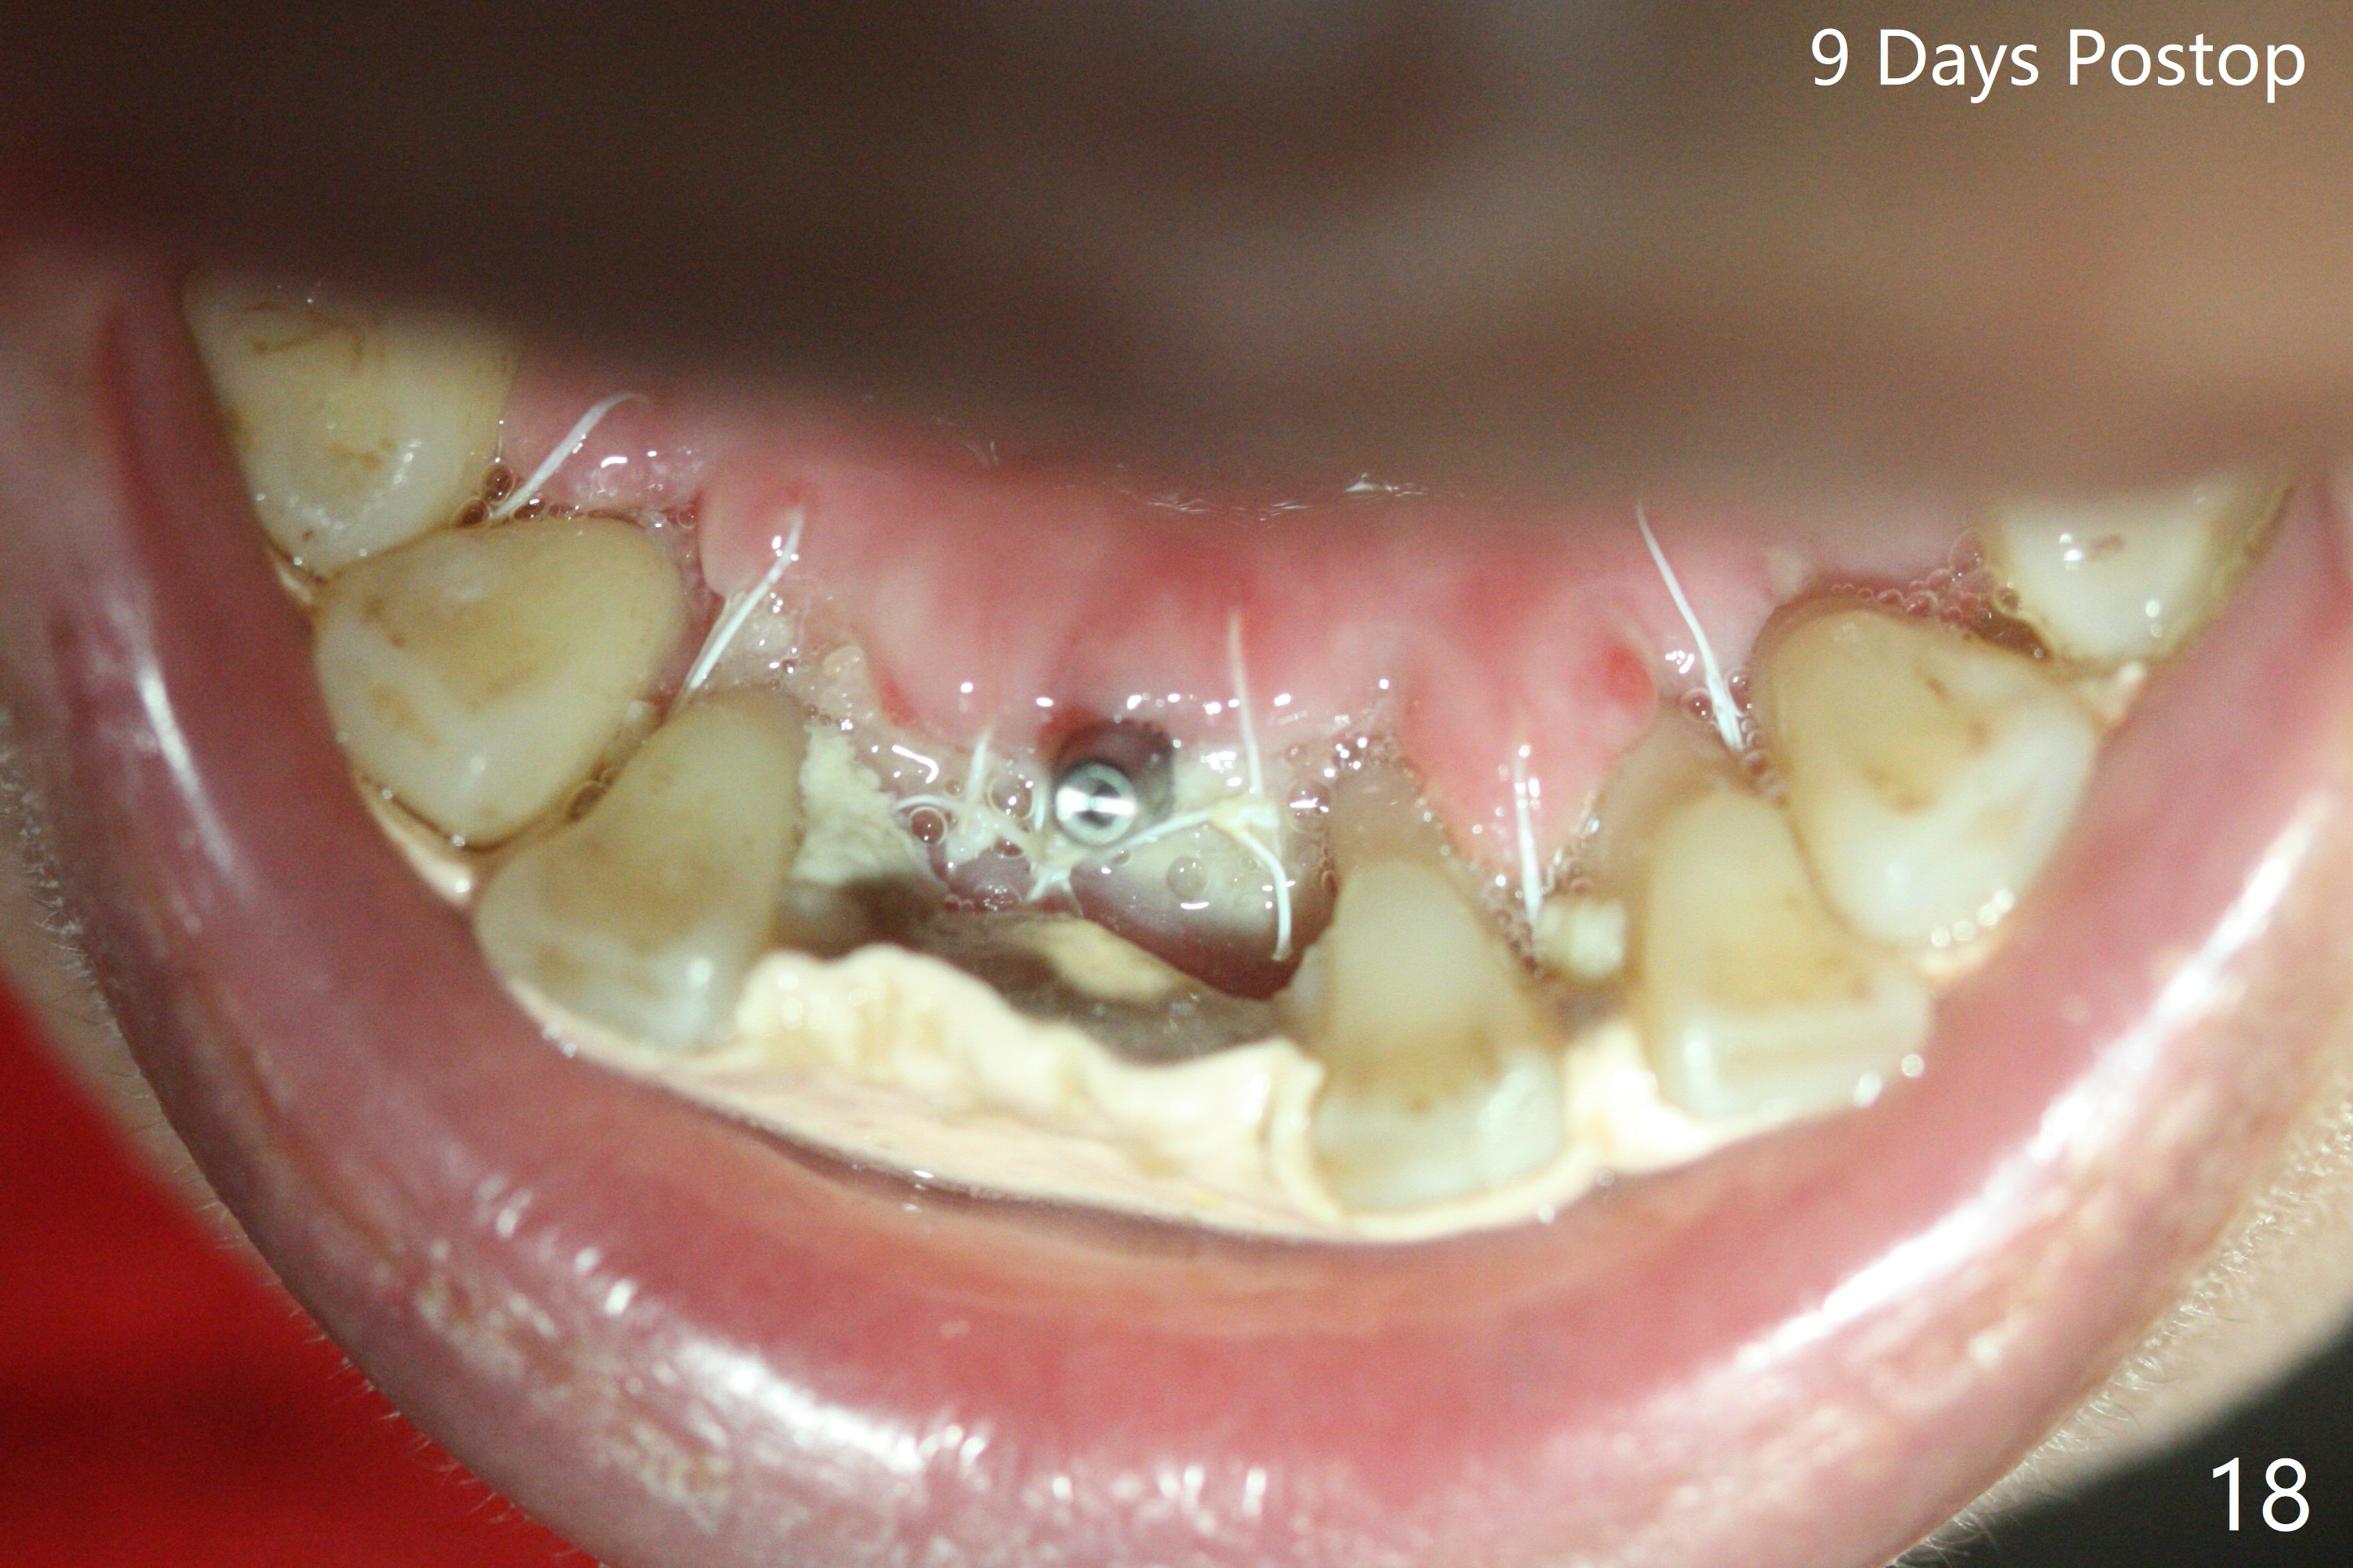

56岁女十分恐惧治疗,缺失右下1,其余切牙由于骨质吸收颊侧移位(图一:1,2),但是她不愿意拔除,同意右下1种植,牙周骨手术,植骨;植体整合后作为支抗,矫正移位下门牙。为了防止忘记舌侧瓣分离,先做舌侧切口(图二),然后颊侧瓣松弛分离(图三),包括使用前牙隧道刀(图四)切断颊侧骨膜,松弛到颊侧瓣能向舌侧牵拉3-4毫米(图五),舌侧瓣骨膜下广泛,深部分离(好像不能切断骨膜,图六),放置导板,磨平狭窄的牙槽嵴(图七:O(osteotomy)),植入2.5x12(4)毫米一段式植体(图八:故意舌侧植入,以便以后矫正),在颊侧骨板打多个出血洞(图八:箭头),然后把在平的器皿上形成的粘性骨板(sticky bone,图九),放置于植体和移位切牙周围(图十),接着使用消毒过的橡皮障punch(图十一(纸头相当于PRF膜;事先给助手示范))在三个PRF膜(图十二)打洞,套在植体和门牙上(图十三: 箭头),防止膜(图十四)和骨块(图十五,十六:*)移位,最后还必须使用最原始方法牙周敷料保护伤口(图十七)。术后9天,舌侧牙周敷料脱落,伤口稍微裂开(图十八)。术后18天撤除敷料,伤口裂开处有新鲜肉芽组织生长(图十九(*:下面是填入的骨粉,将是增宽的牙槽嵴(如果你是乐观主义者)),二十)。病人十分感激我们帮助她度过难关。她的确有sleep apnea,否定tongue thrust。术后三个月植体周围没有明显骨质吸收(图二十一至二十三),左下1,2轻度反合(图二十四),植体周围软组织健康(图二十五),5-5安置矫正器(图二十六,二十七,12 niti)。一周后下切牙向舌侧移动(图二十八),左下1,2反合纠正(图二十九)。再一周变化不大(图三十),植牙圈有些松动,两周后将重做临时牙冠,槽往舌侧移动。结果病人提前回来,植牙槽舌侧移位。一周后右下2不适(图三十一),尝试近中牵引(图三十二)。